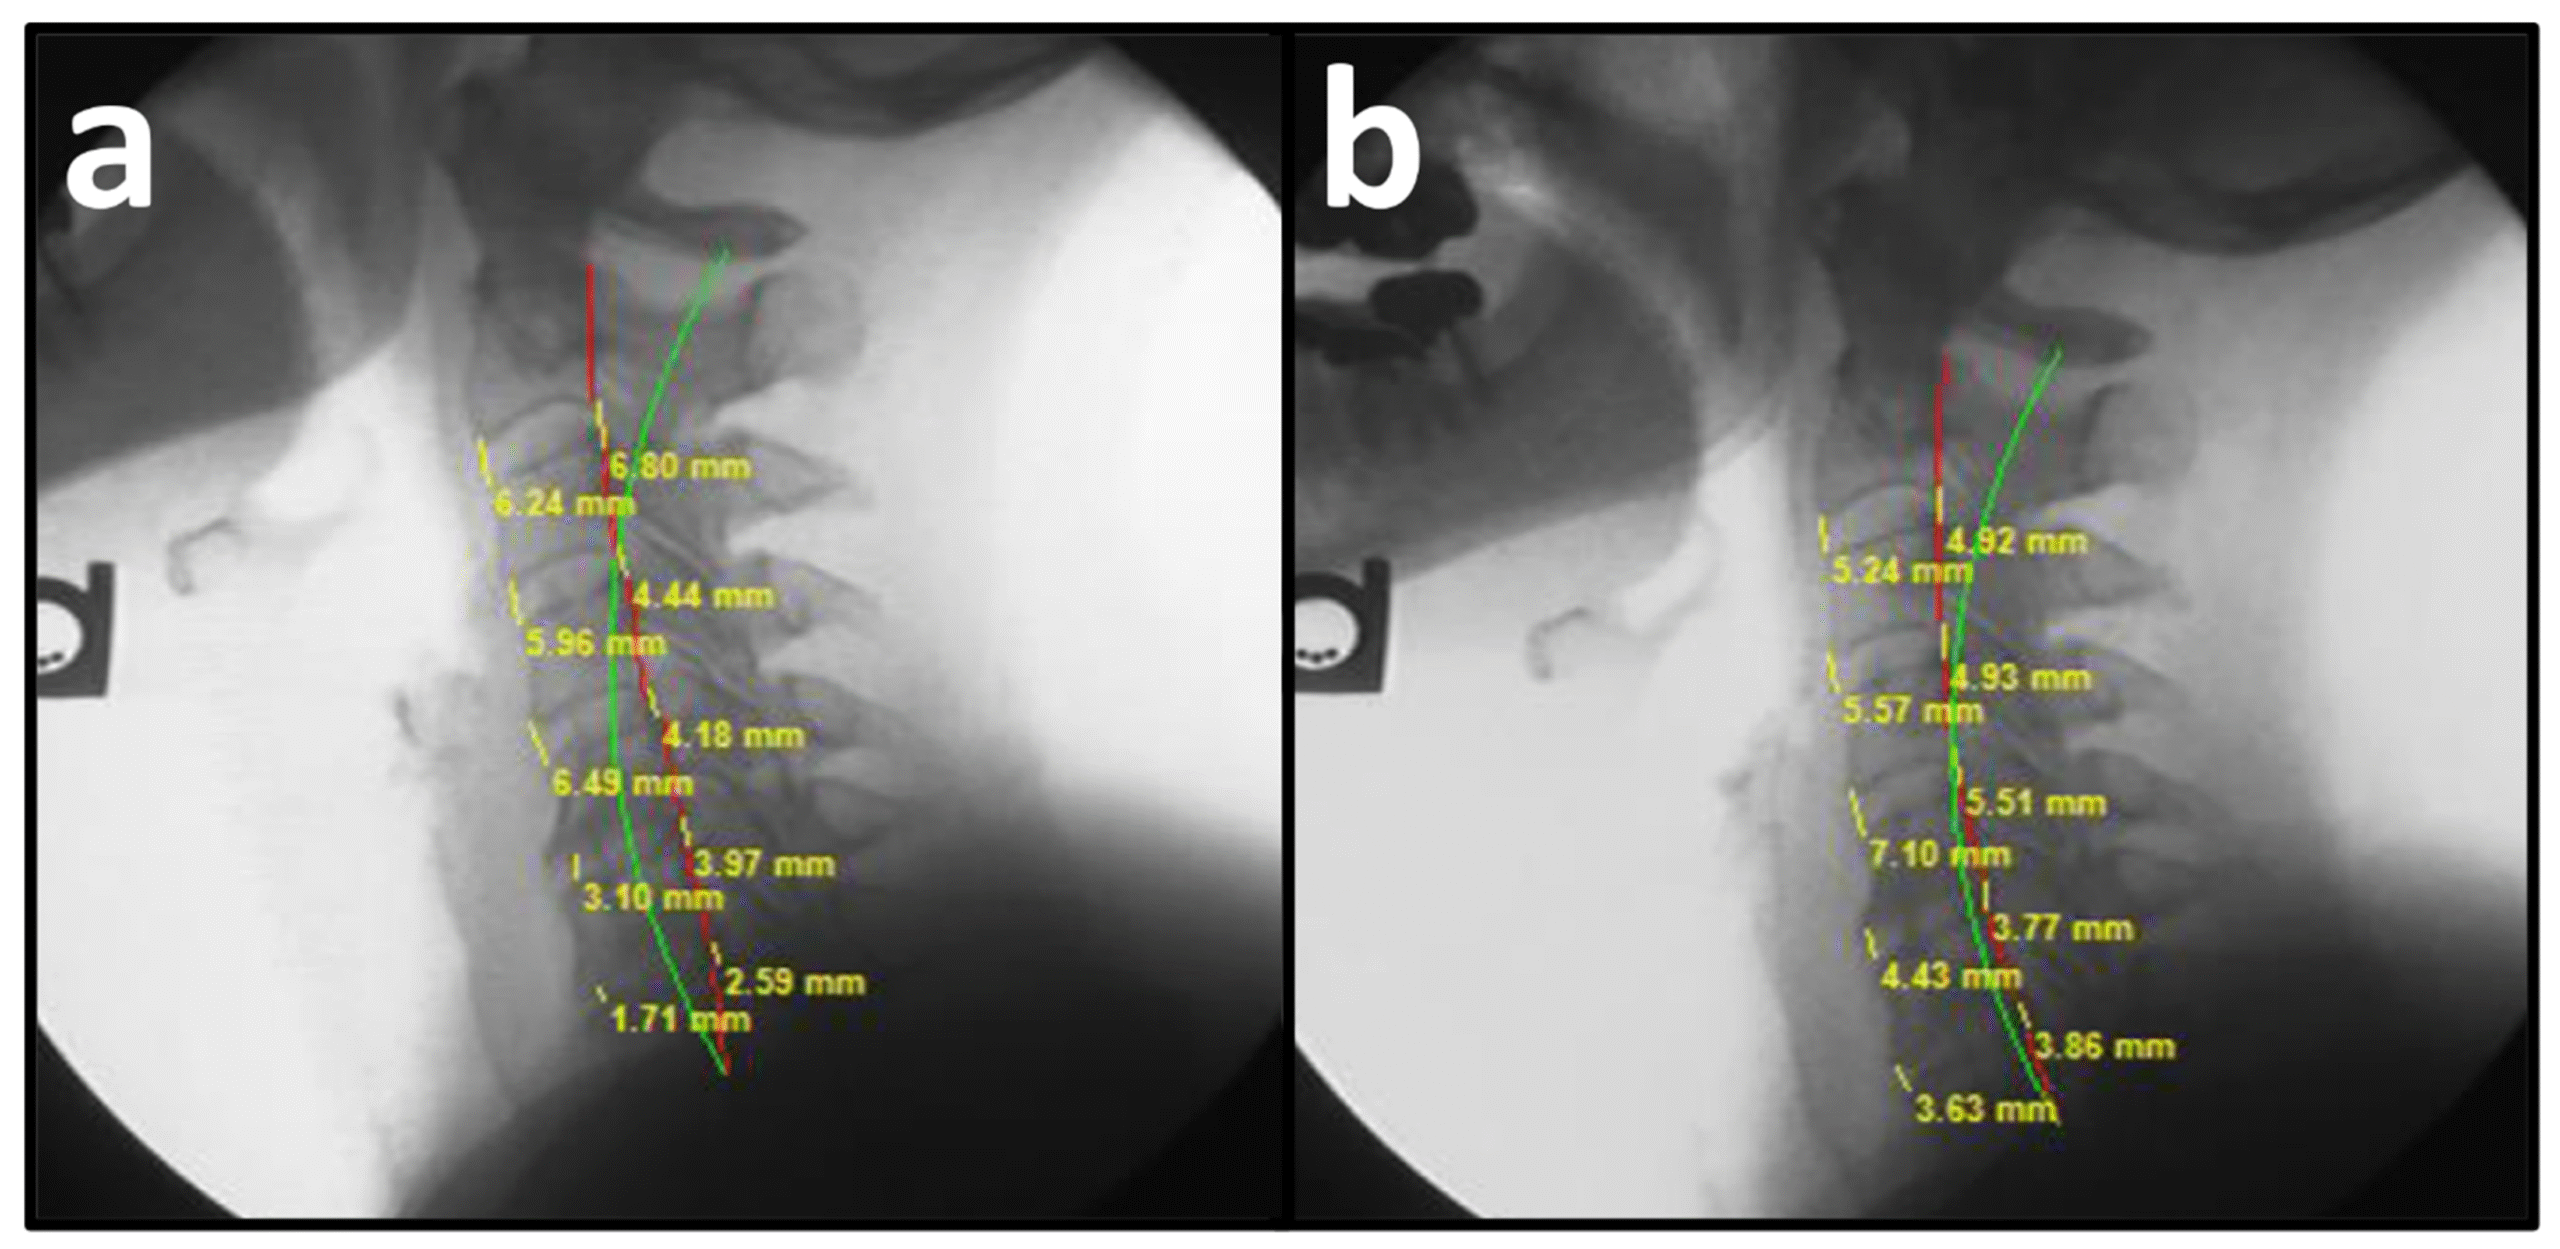

New Study: Disc Heights, Pain, Function, Posture, & Cervical Curve Improved with CBP Methods New Study: Disc Heights, Pain, Function, Posture, & Cervical Curve Improved with CBP MethodsBy MyChiroPractice|2026-02-24T16:46:07+00:00February 24th, 2026|Read More